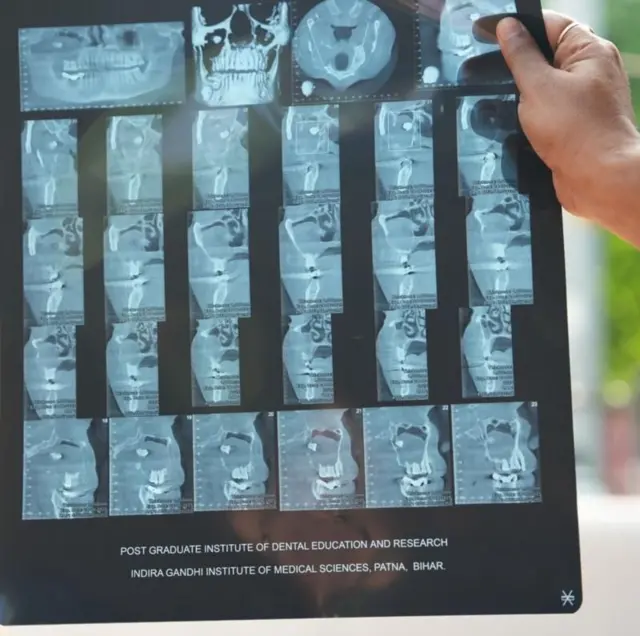

"મારું બધું કામ બંધ થતું જઈ રહ્યું હતું. જે બાદ મેં જૂનમાં આઇજીઆઇએમએસમાં દાંતના ડૉક્ટરને બતાવ્યું. ડૉક્ટરે મારો સીબીસીટી સ્કૅન કરાવ્યો. પછી ખબર પડી કે મારી આંખમાં તો દાંત છે. 11 ઑગસ્ટના રોજ ડૉક્ટરે મારું ઑપરેશન કર્યું. હવે હું સંપૂર્ણપણે સ્વસ્થ છું."

સીબીસીટી એટલે કે કોન બીમ કમ્પ્યૂટેડ ટોમોગ્રાફી. સરળ શબ્દોમાં આ એક પ્રકારનો ઍક્સ-રે છે. જે મૅક્સિલોફેશિયલ એરિયાનો ઍક્સ-રે કરીને થ્રી ડી તસવીરો બનાવે છે.

દર્દી રમેશકુમારે જ્યારે સીબીસીટી કરાયા બાદ ખબર પડી કે ફ્લોર ઑફ ધ ઑર્બિટમાં દાંતનાં મૂળ છે.

પ્રિયાંકર કહે છે કે, "આ મામલામાં દાંતનાં મૂળ ફ્લોર ઑર્બિટમાં હતાં. જ્યારે તેનો ક્રાઉન પોર્શન (દાંતનો સફેદ ભાગ) મૅક્સિલરી સાઇનસમાં હતો. આ દાંત પોતાની નૉર્મલ જગ્યાએ નહોતો બન્યો તેથી શરીર માટે એ ફૉરેન બૉડી હતો."

દાંત આંખના ફ્લોર ઑફ ધ ઑર્બિટમાં ઊગી રહ્યો હતો, તેથી જ્યાંથી ઘણી બધી નસો નીકળે છે, તેથી આ એક મુશ્કેલ સર્જરી હતી.